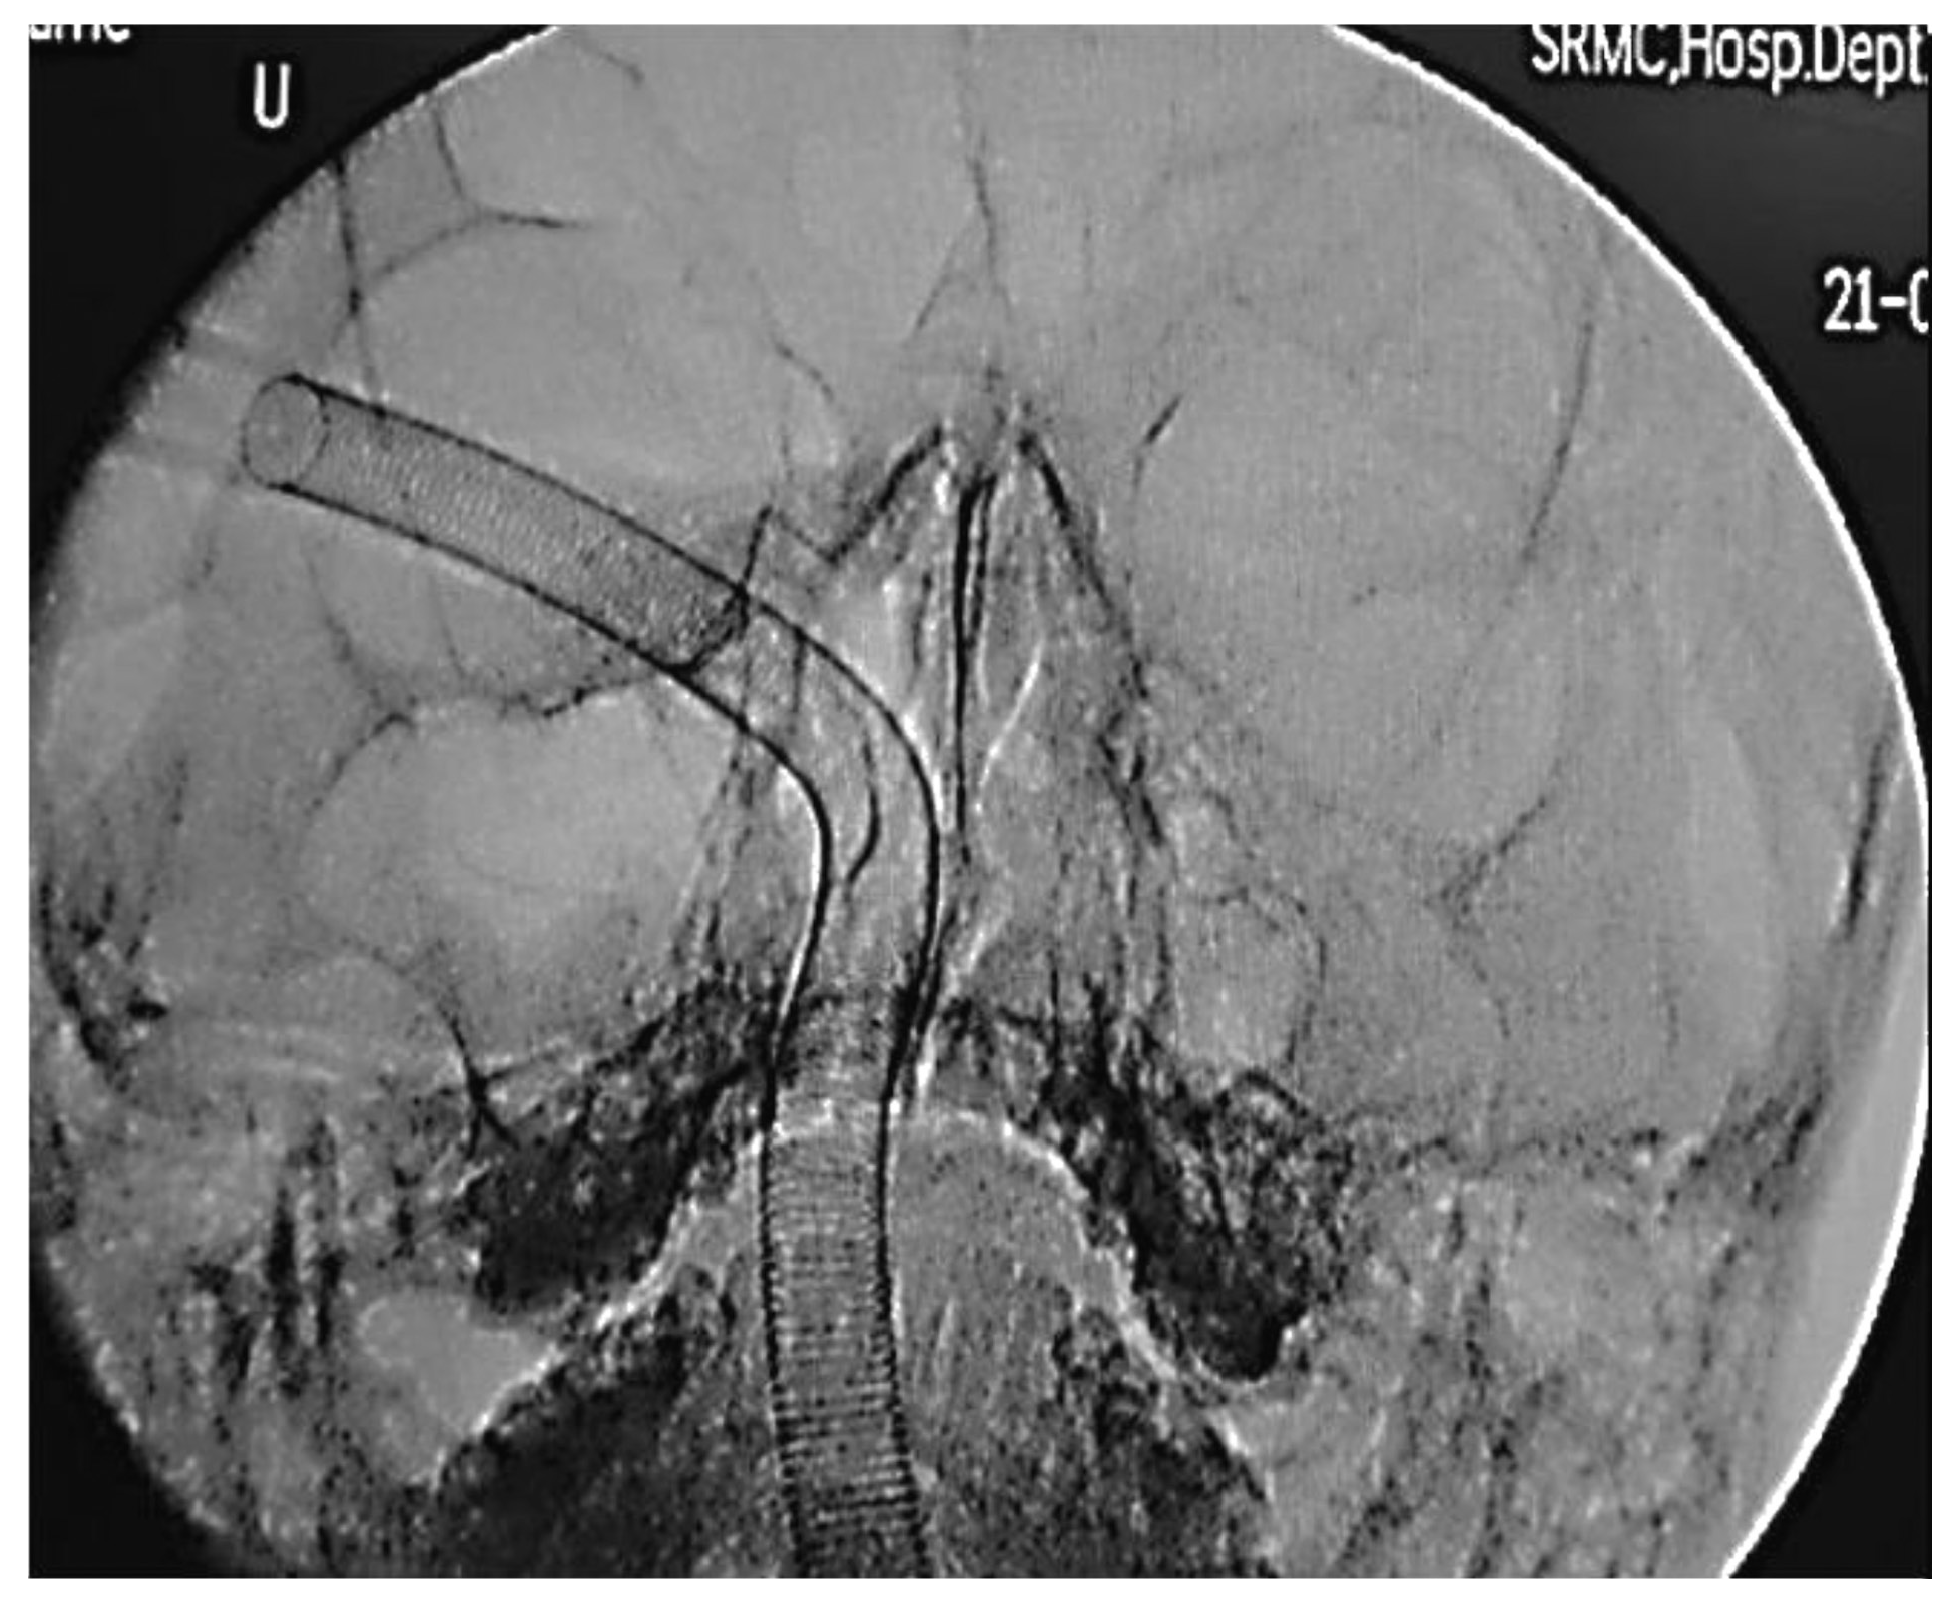

Figure 6.

Pre-operative CT-PNS image of a patient.

Pre reduction C-arm alignment at 0°.

Pre reduction C-arm alignment at 30°.

Pre reduction C-arm image at 0°.

Patient was placed in anti-Trendelenburg position with neck in extended position. To minimize the magnification, the X-ray source was kept far away and intensifier kept close to patient’s vertex. The directions of X-rays are from chin to vertex appropriately at an angle of 5 degrees from menton to bregma in automatic pulsed fluoroscopy mode. Personal protective equipment such as lead aprons, thyroid collars, and Goggles were used.